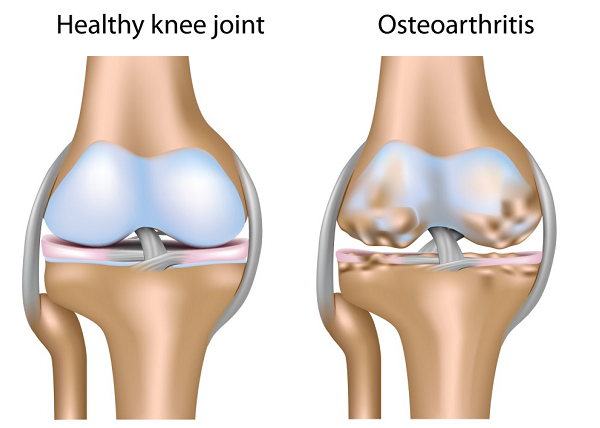

Osteoarthritis:

Osteoarthritis is the most common types of arthritis resulting from damaged cartilages. Osteoarthritis is more common with joints that bear weight; such as, knees, spine, hip and feet. Every two bones, forming a joint, are cushioned with rubbery tissues known as cartilages. Any wear and tear of this cartilage results in osteoarthritis.

Causes:

- With age our bones and cartilages get worn out

- Obesity that puts on excessive pressure on bones and cartilages that constitute joints bearing weight

- Certain bone injury

- Family history of osteoarthritis makes you prone to this condition, especially when proper preventive measures are not adopted

- People involved in some kind of physical activities that require excessive use of joints are prone to knee osteoarthritis

Symptoms:

- Morning stiffness or experiencing the same after long periods of rest

- Pain felt deep within the bones

- Joint pain getting severe with later part of the day

- You can sense swelling of joints

- Your joints may feel a little warm

- A grating sound resulting from roughened and worn out cartilages that rub against each other

- Difficulty in climbing stairs, combing hair, bending over, etc. In short, you may experience hindered motion

- Numbing and tingling of the affected area. This condition is more common with spine osteoarthritis

- Bony spurs or bone enlargement on fingers

- Formation of Bunions on big toes. It is a kind of bony enlargement peculiar to toes.